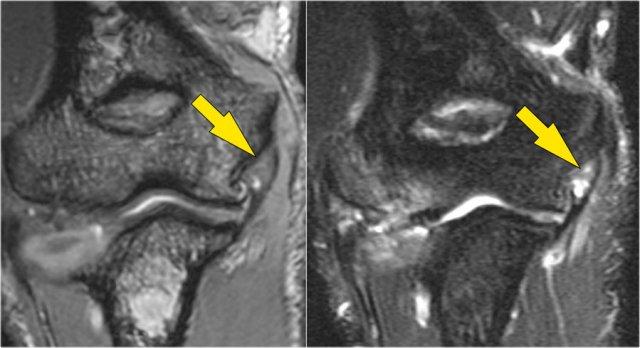

Sagittal view:

- Một lần nữa, hình ảnh đặc trưng của phù tủy xương thường gặp trong trật khớp khuỷu tay ra sau với vết dập ở phía trước của chỏm xương quay (mũi tên đỏ) và ở phía sau của chỏm con xương cánh tay.

- Chỏm quay phải đã va chạm vào phần sau của chỏm con xương cánh tay.

Cấu trúc phía sau chỏm quay là dây chằng vòng.

Nó không đều và dày lên do hậu quả của trật khớp ra sau.